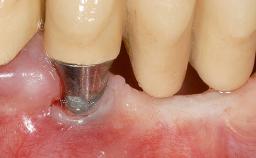

Periodontal Plastic Surgery and Prosthetic Procedures to Treat Peri-Implant Soft-Tissue Dehiscences

A 30-year-old woman was referred by her general dentist for evaluation of an esthetic complication related to previous implant treatment for congenitally missing maxillary lateral incisors. The patient’s chief complaint was the inadequate esthetic appearance of her smile. The case demonstrates the use of a combined approach to achieve optimal results. Two different flap designs - a tunnel technique and a coronally advanced flap - are employed based on the surgical objectives for the affected site.